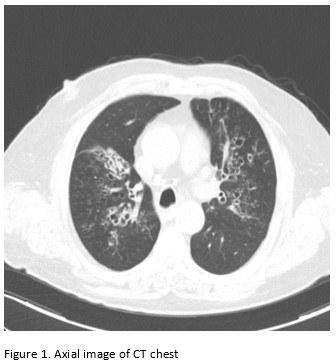

A 65-year-old male with poor healthcare follow-up presents to the pulmonary clinic with “years of breathing problems”. He reports shortness of breath and cough productive of grayish-brown sputum. He denies fevers, chills, weight loss, hemoptysis and night sweats. He denies recent travel history. His physical exam is significant for scattered wheezes bilaterally. Labs are significant for peripheral eosinophilia of cells/microL (21.7% eosinophils) and elevated total Ig E level of 2385 IU/ml. Representative images of his CT chest are shown below.

Images